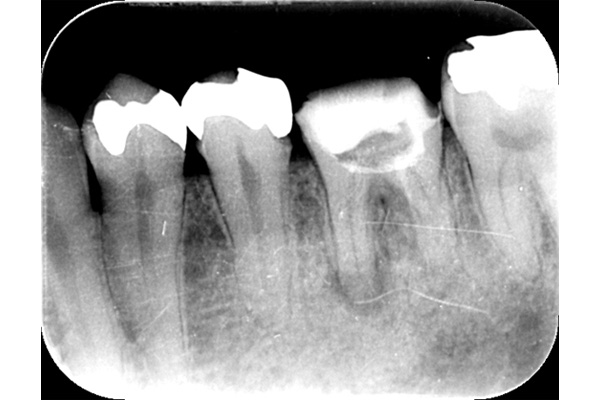

左のレントゲンでは破折したかどうかはわからないが、虫歯になっている部分をとっていくと歯が割れているのがはっきりとわかりました。

歯が割れるケースで多いのが金属の土台(メタルコア)が入っている場合です。特に根の中に長いものが入っていると、歯を割る力が強くかかるため、割れることが多いです。

こちらの写真は違和感があるということでレントゲンを撮ったが異常は見つからなかった。しかし、1ヶ月後にもう一度撮影すると、歯が割れているのがわかりました。また、歯の周りの骨の部分がやや黒くなっているのも分かります。

また、金属の土台がはいっていなくても、根の治療を行った歯にブリッジが入っている場合、負担が大きくなり、

神経がある歯よりも脆い神経を取った歯は割れてしまうことがあります。